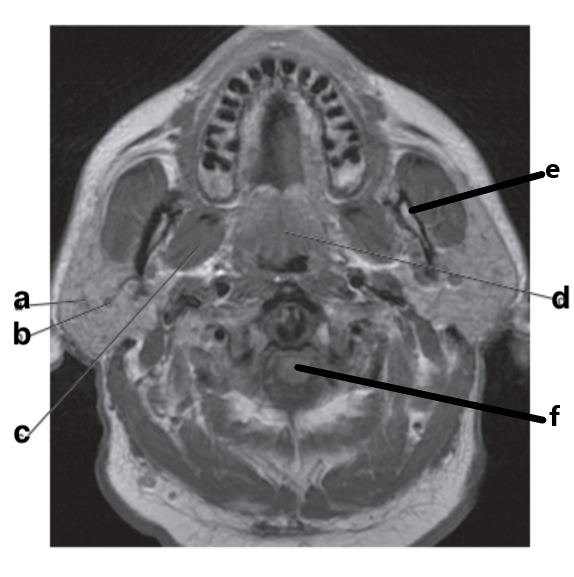

Thyroid gland

Mandible

Parotid gland

Internal carotid artery

Cervical Spinal cord

Submandibular gland